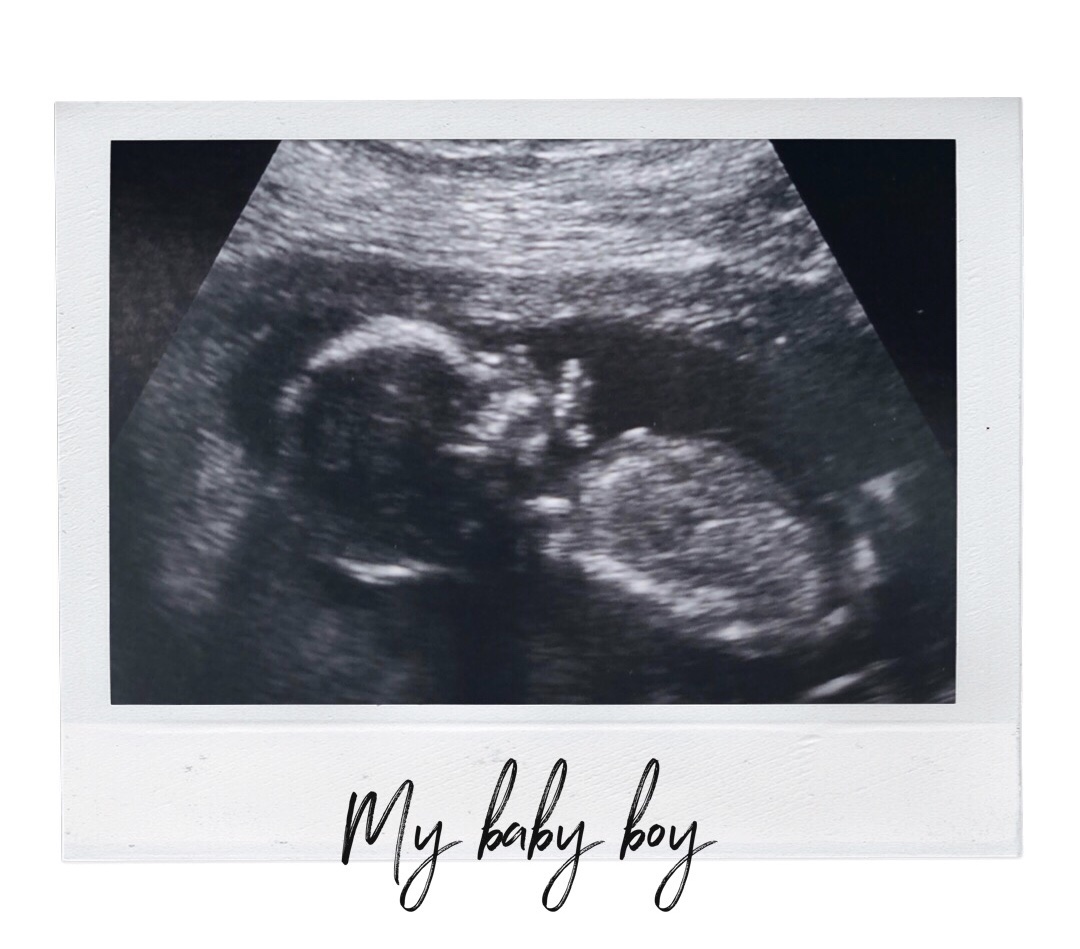

I was obviously very worried and scared, but the specialists knew what they were looking for and put me at ease. I was so amazed at my first weekly appointment, I had a 40 minute ultrasound scan where they checked his brain, heart and blood levels. I couldn’t believe the technology, there was my baby boy and his beating heart, I could see the valves and the blood pumping round, it was fascinating.

I then attended weekly scans for most of my pregnancy, we had a little scare where the levels became boarderline and I had to go see another two specialists but my little man stayed strong and he remained just below the level for further treatment.